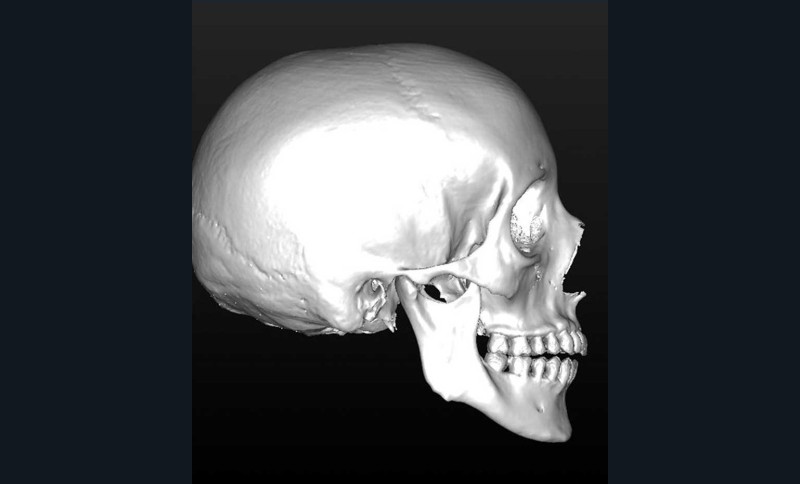

La mandibule est maintenue stable pendant l’examen. Sa position varie selon la typologie du patient. En cas de normo ou d’hyper-divergence, la mandibule est stabilisée en relation centrée (fig. 1).

Les données natives en format DICOM sont ensuite traitées (phase de segmentation) :

– suppression des artefacts ;

– élaboration des images 3D en isolant des différents constituants anatomiques : crâne et maxillaire, mandibule, dents, dispositifs d’orthodontie, implants endo-osseux et prothèses conjointes éventuelles, etc.